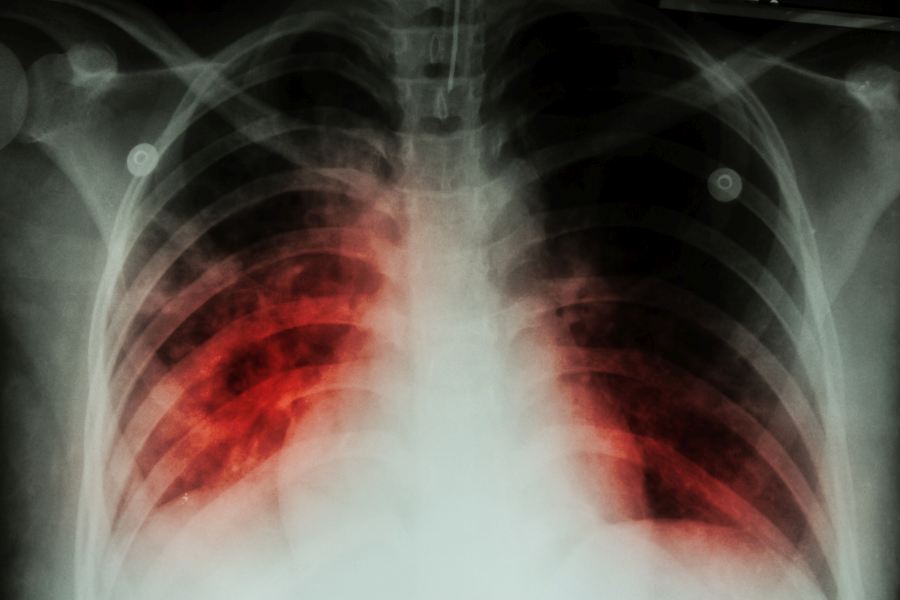

W zaawansowanej postaci gruźlicy występują zmiany gruźlicze w płucach, które są widoczne na zdjęciach radiologicznych klatki piersiowej.